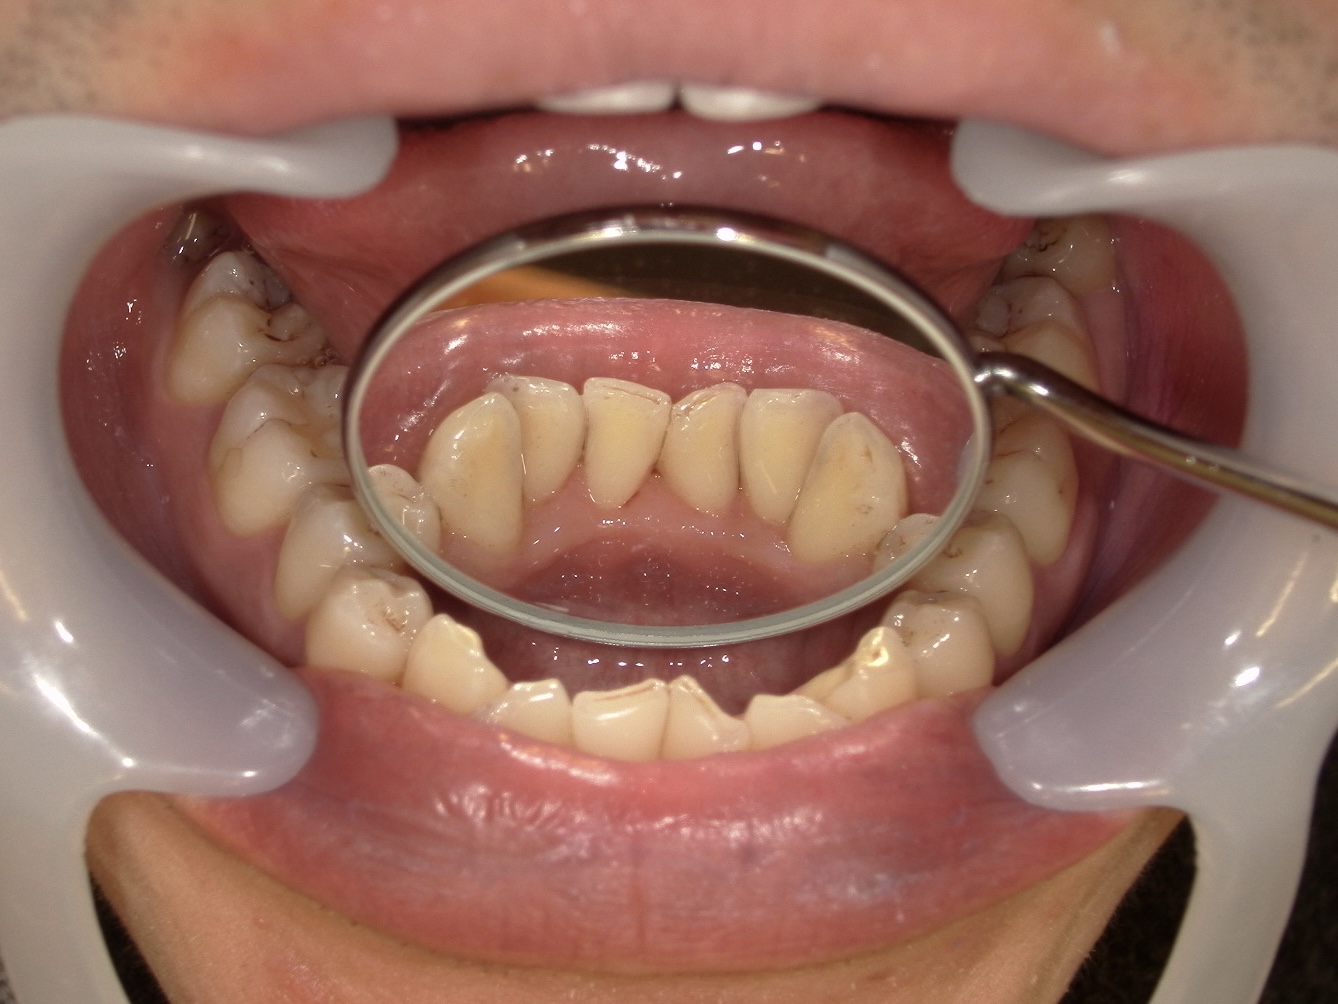

◆クリーニング前の状態(染め出し後)

当院ではクリーニングを行う前に、染め出しを行います。歯垢を染めることによって、「こんな場所にこんなにみがき残しがありますよ」と可視化することで患者様により分かりやすく見ていただくことができます。

写真をご覧いただくと分かる通り、

下の前歯の裏側には染め出し液が広範囲に付着しているのが分かります。

この部分は、

鏡ではほとんど見えない

舌が常に当たる

唾液腺が近く、歯石が付きやすい

という特徴があり、セルフケアだけで完全にきれいに保つのが非常に難しい部位です。